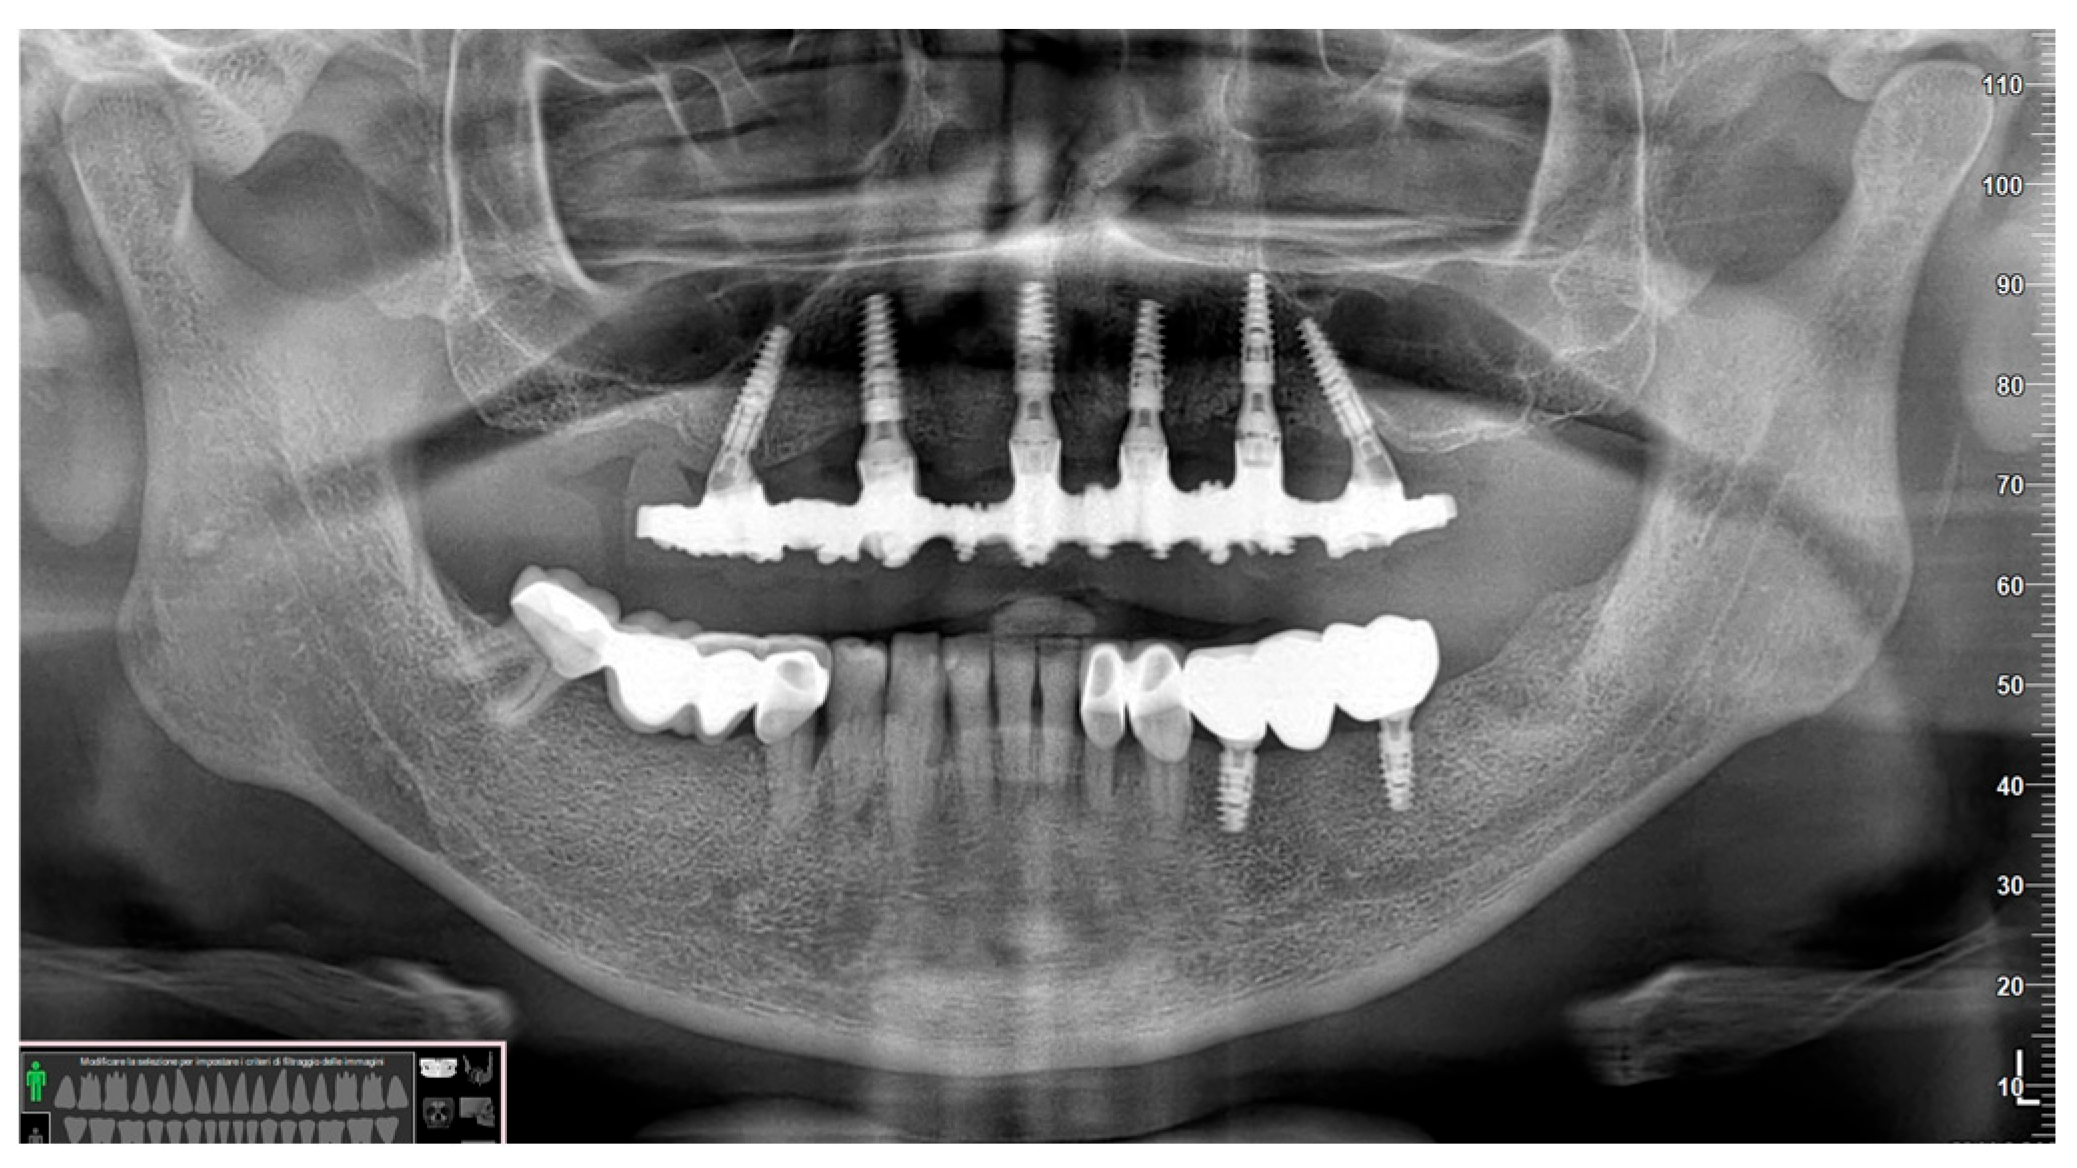

2.3. Surgical Procedure

2.5. Prosthesis Generation

3. Results